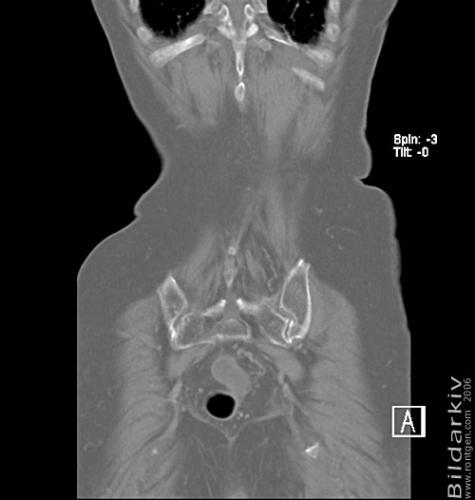

CT colon 45

Datortomografi av tjocktarmen (colon) med infunderad luft i tarmen samt med kontrast i blodbanan. Koronar bildserie.

CT multislice 16